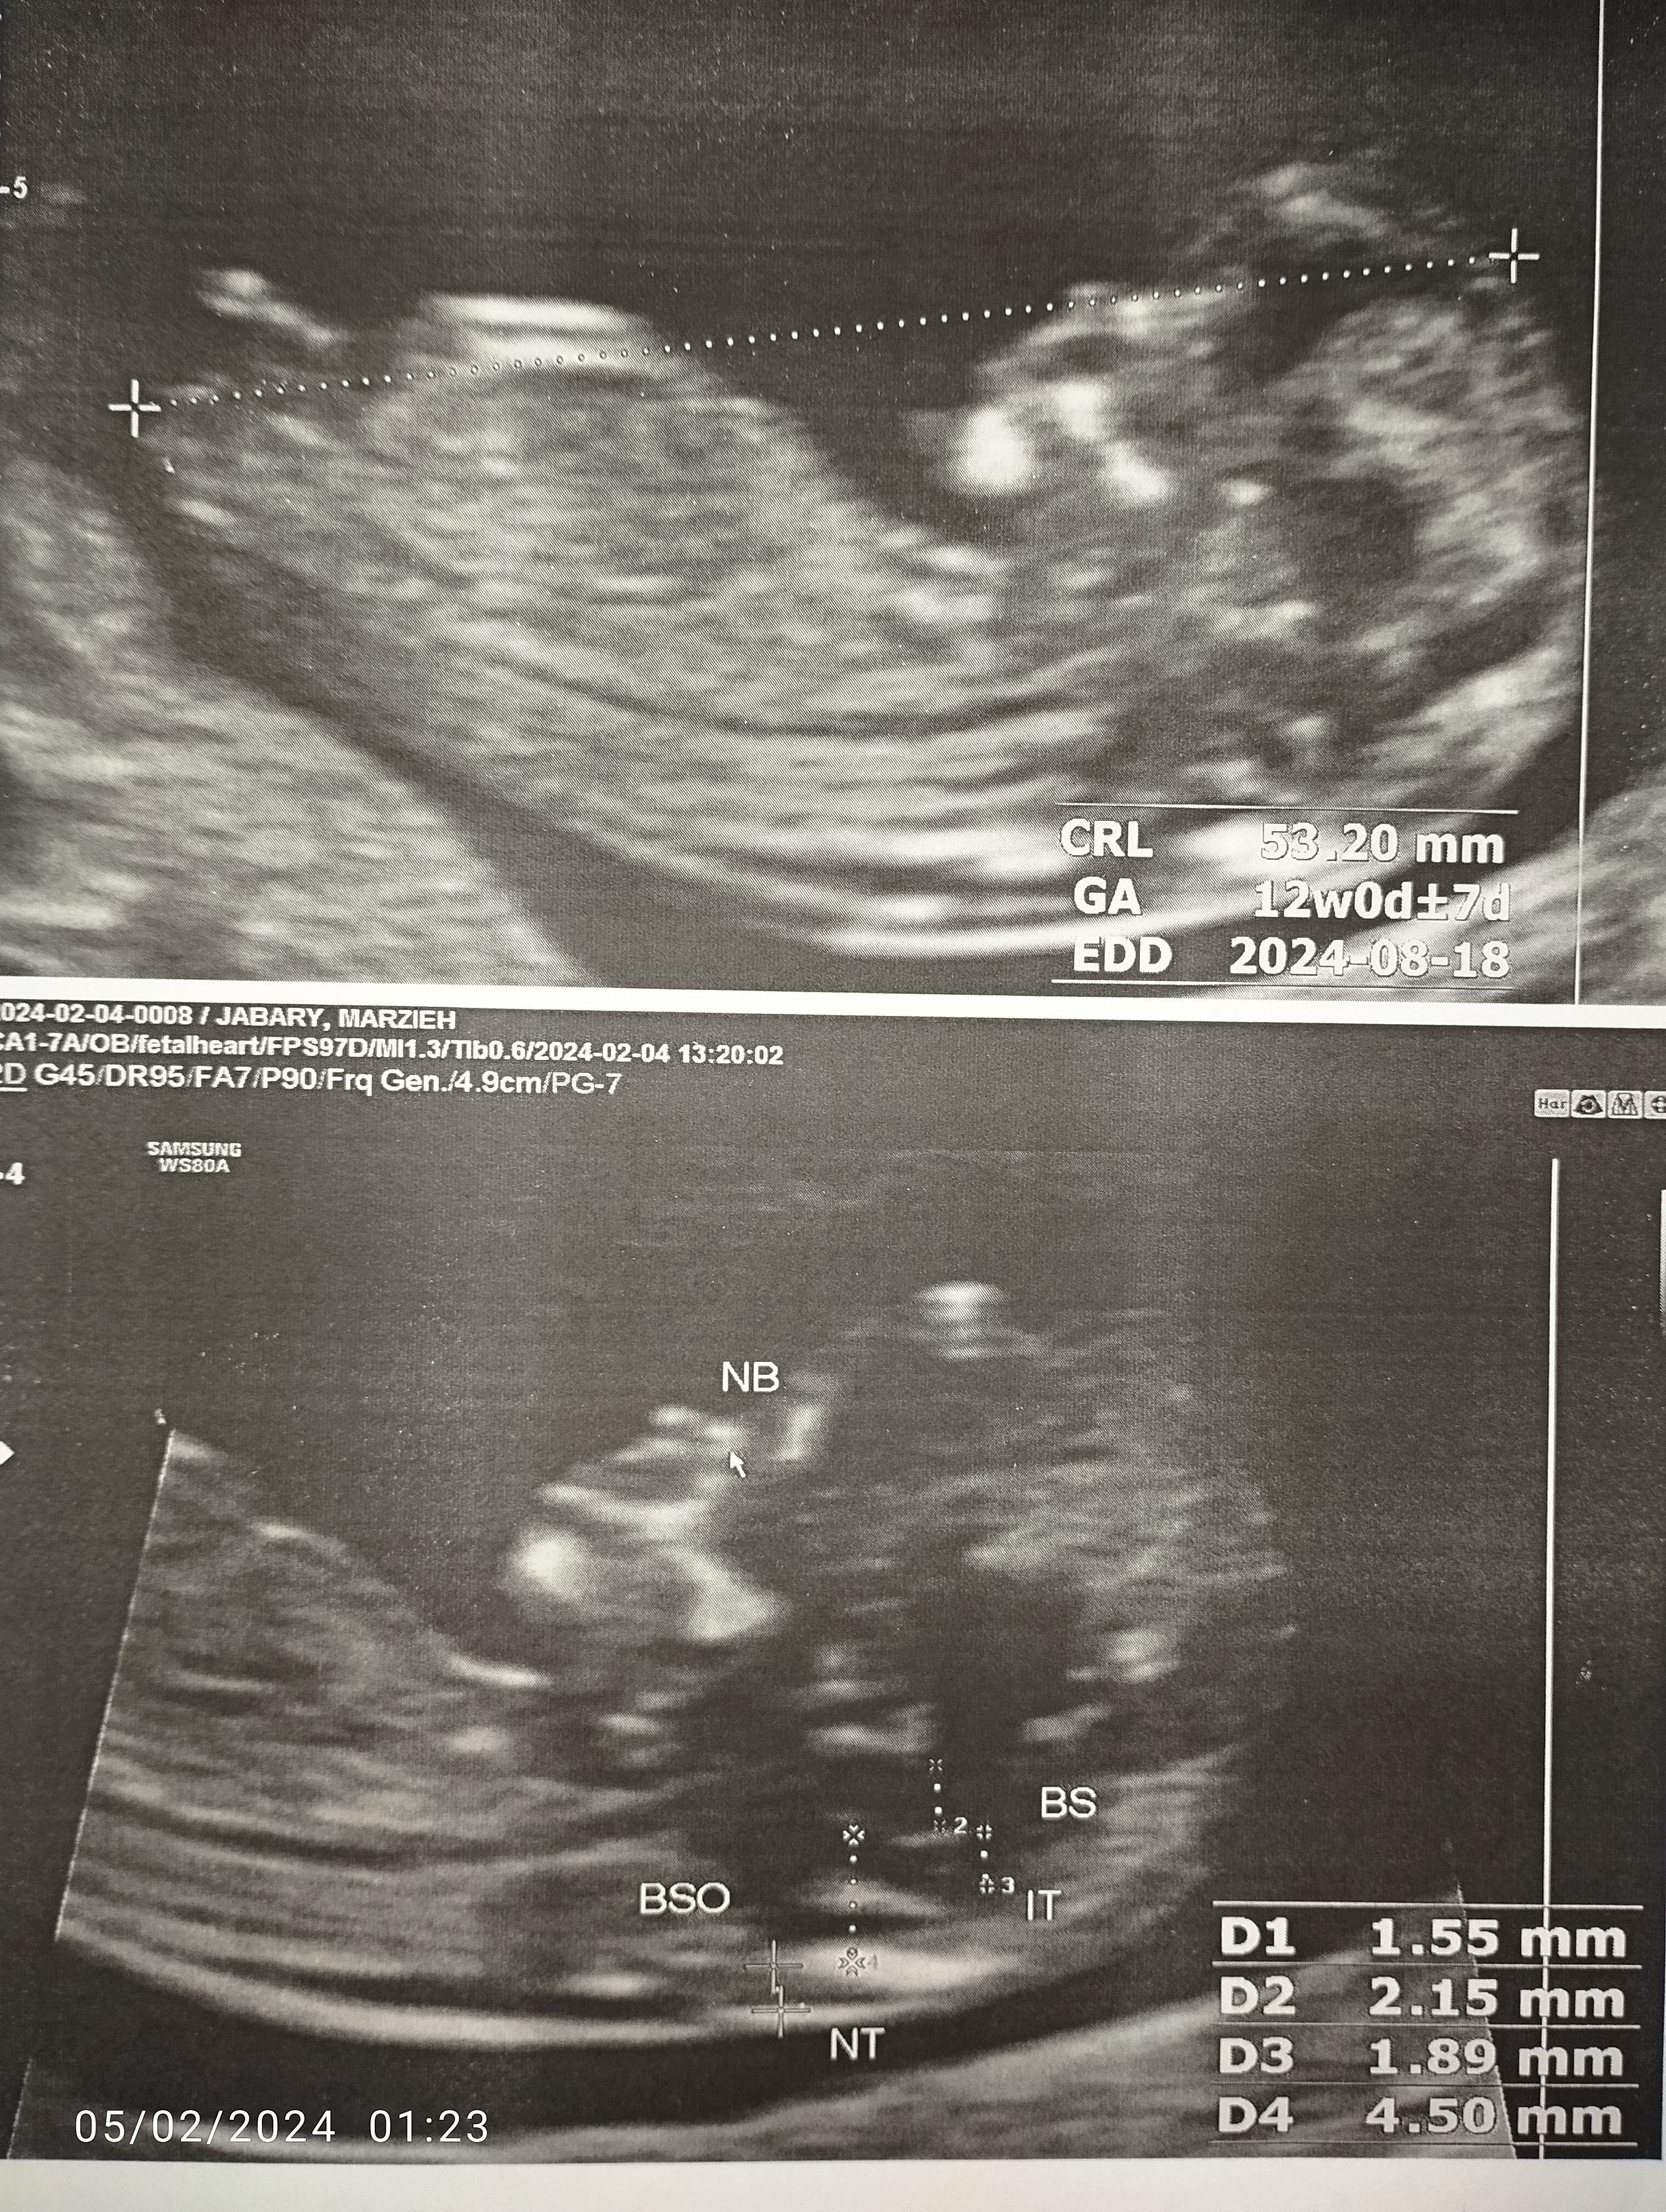

نه عزیزم سونوی اسی رو میگم برامدگی داره سونوی شما پایین رو من ندیدم تو عکس فقط انگار سر و شکم نینی جون افتاده

نه عزیزم سونوی اسی رو میگم برامدگی داره سونوی شما پایین رو من ندیدم تو عکس فقط انگار سر و شکم نینی ج ...